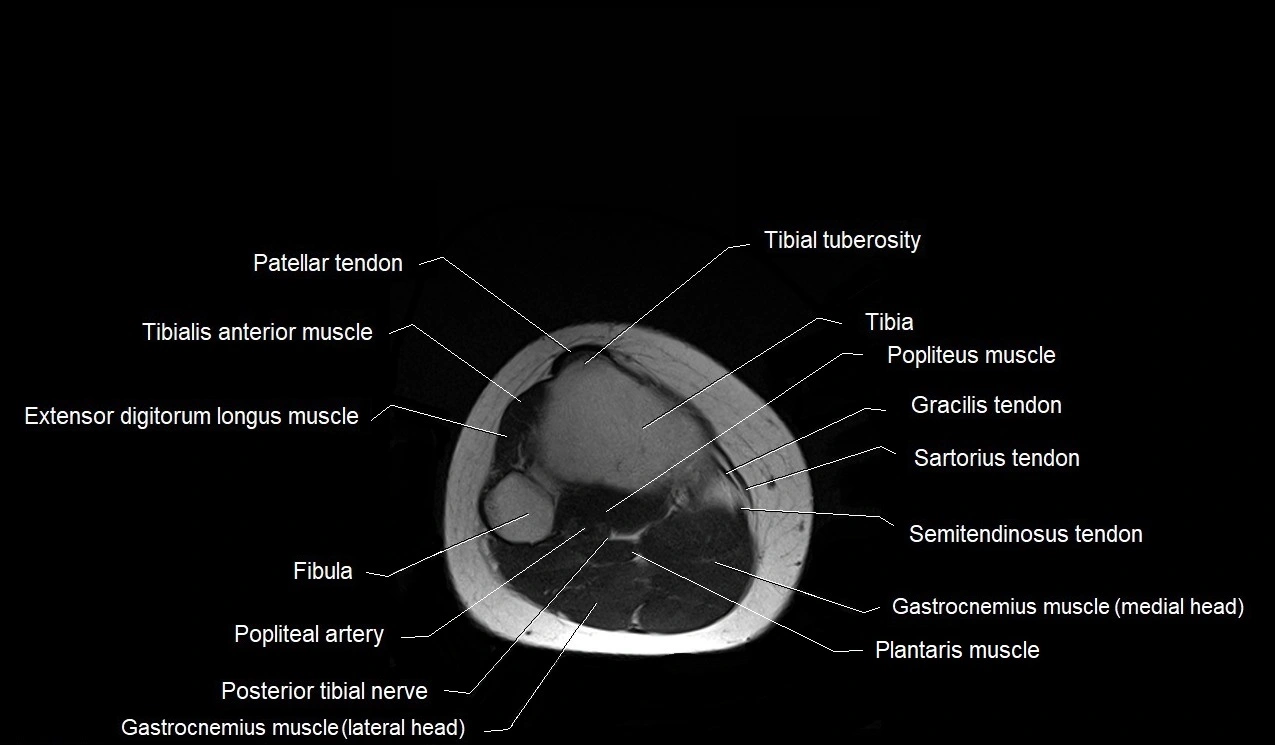

- Tibia

- Tibial tuberosity

- Tibialis anterior muscle

- Fibula

- Popliteus muscle

- Popliteal artery

- Tibial nerve

- Extensor digitorum longus muscle

- Gastrocnemius muscle

- Plantaris muscle